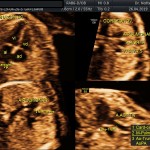

- Las Estructuras Anatómicas Fetales, diagnóstico precoz de Malformaciones (sensibilidad del 80%).